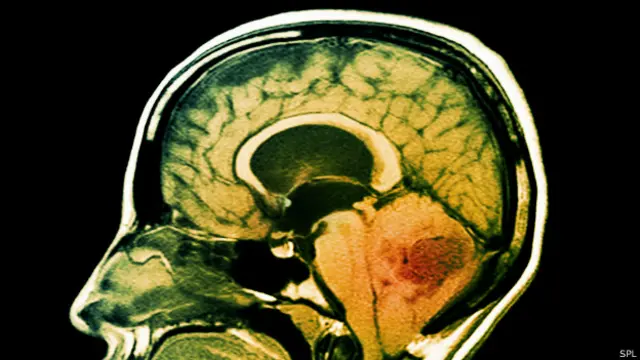

Kaynak, SPL

Bu türler, beyin kanseri, ince bağırsak ve pankreas gibi kanserleri de kapsıyor.